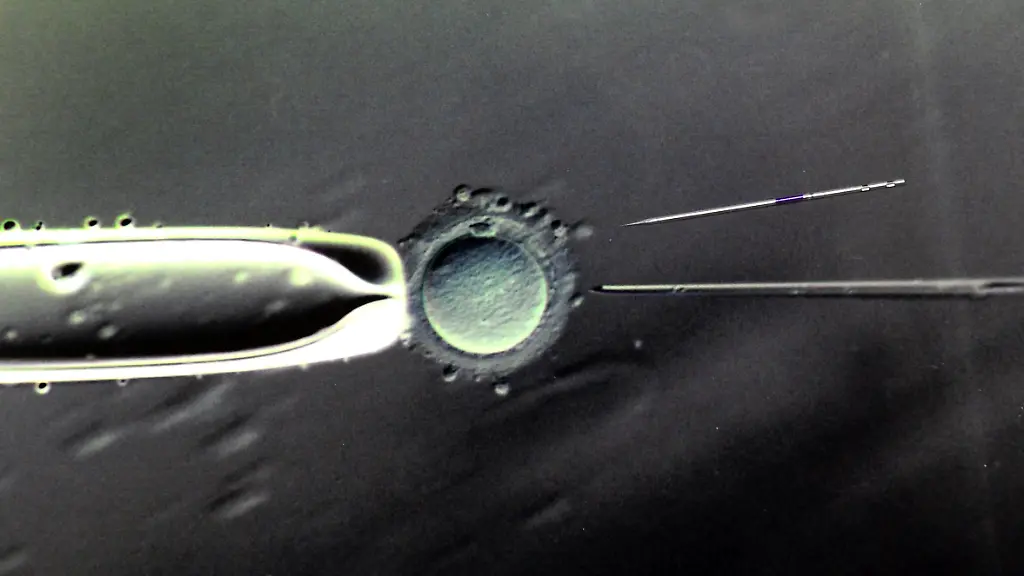

Eine schwere Erkrankung oder eine Fehlgeburt: Wer das beim Kinderwunsch ausschließen will, dem gibt die sogenannte Präimplantationsdiagnostik Hoffnung - jetzt auch in der Schweiz. Sie erlaubt die umstrittene Methode aber nur in bestimmten Fällen.

Ab dem 1. September dürfen Ärzte in der Schweiz nach einer künstlichen Befruchtung den Embryo auf bestimmte genetische Merkmale untersuchen. Die Richtlinien sind so eng gefasst wie in Deutschland: Getestet werden darf nur, wenn die Eltern eine schwere Erbkrankheit haben oder Gen-Anlagen, die eine Tot- oder Fehlgeburt wahrscheinlich machen. Embryonen mit Schäden werden der Mutter nicht eingepflanzt. Untersuchungen anderer Eigenschaften, wie etwa Geschlecht oder Haarfarbe, bleiben verboten.